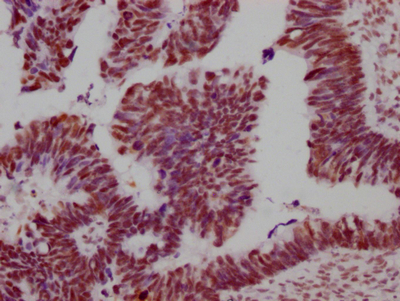

IHC image of CSB-RA149196A0HU diluted at 1:100 and staining in paraffin-embedded human ovarian cancer performed on a Leica BondTM system. After dewaxing and hydration, antigen retrieval was mediated by high pressure in a citrate buffer (pH 6.0). Section was blocked with 10% normal goat serum 30min at RT. Then primary antibody (1% BSA) was incubated at 4℃ overnight. The primary is detected by a Goat anti-rabbit IgG polymer labeled by HRP and visualized using 0.05% DAB.

IHC image of CSB-RA149196A0HU diluted at 1:100 and staining in paraffin-embedded human glioma cancer performed on a Leica BondTM system. After dewaxing and hydration, antigen retrieval was mediated by high pressure in a citrate buffer (pH 6.0). Section was blocked with 10% normal goat serum 30min at RT. Then primary antibody (1% BSA) was incubated at 4℃ overnight. The primary is detected by a Goat anti-rabbit IgG polymer labeled by HRP and visualized using 0.05% DAB.